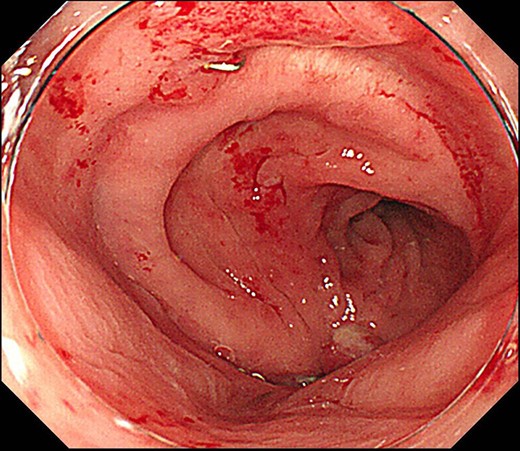

Case 2 was a 58-year-old man with a BMI of 30.3 kg/m2. Robot-assisted LAR and ileostomy was performed for lower rectal cancer over the past 2017 years, and a 1/2 circumferential fistula around the 6 o’clock direction was recognized on postoperative colonoscopy (Fig. 4). The patient was diagnosed as having a grade A anastomotic leakage without symptom because of the anastomotic leakage. He was discharged on POD 26 and was followed up on an outpatient basis. Contrast imaging performed simultaneously with endoscopic examination 6 months after the operation showed remarkable improvement of the abscess cavity, but it still remained (Fig. 5a and b). The anastomotic leakage improved 11 months after surgery (Fig. 6), but a polyp was found on the anal side 2 cm from the anastomotic site and was resected. Adenocarcinoma, pTX, ly0, v0, pHMX, and pVMX were diagnosed. The tumor was followed up because the depth of penetration, the deep stump, and the horizontal stump remained unknown (Fig. 7). Regarding the polypectomy site, no abnormality was found in the examination 8 months after resection of the polyp. Therefore, ileostomy closure was performed 18 months after the first operation (Fig. 8). Postoperatively, it took some time to improve the intestinal movement with paralytic ileus, but the patient was discharged 18 days after surgery. The Wexner score one month after closure was 18 points and still showed high anal dysfunction but the patient was under observation at the outpatient department.

Colonoscopy shows a true lumen (circle) and an abscess cavity (arrow) with drainage of pus.